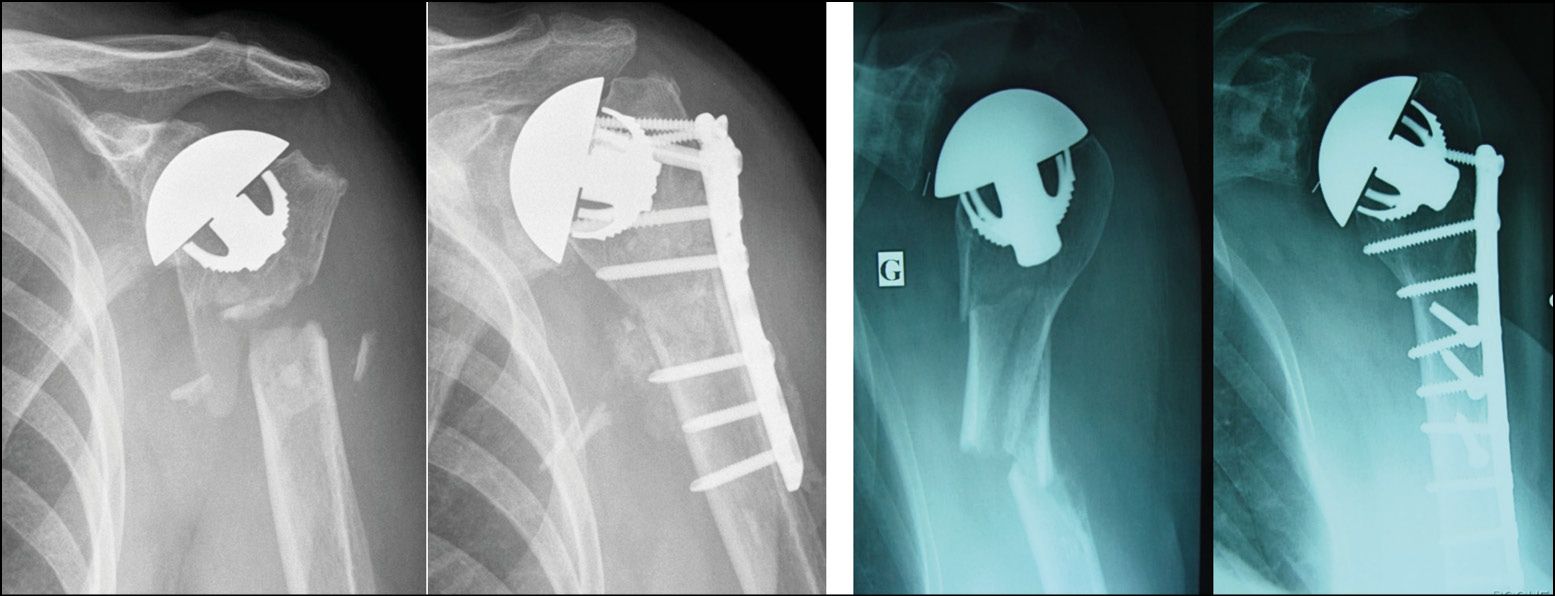

Malunion of the proximal humerus, if recent enough to have not affected the glenoid cartilage, is again a good indication: a stemless humeral implant makes it possible to restore the humeral head without any of the constraints caused by offsets or tuberosity transfer (Fig. 11).[4] Ballas R, Teissier P, Teissier J. Stemless shoulder prosthesis for treatment of proximal humeral malunion does not require tuberosity osteotomy. Int Orthop. 2016; 40:1473-9. doi: 10.1007/s00264-016-3138-y.

Osteoarthritis with rotator cuff tear in a young subject is a good indication for a reverse replacement because the absence of a stem makes the procedure less invasive (Fig. 14). Complex malunion can also be treated with a stemless reverse TSA, since the procedure removes the need for any diaphyseal or tuberosity transfer thus avoiding any corrective osteotomy which is rarely beneficial (Fig. 15).